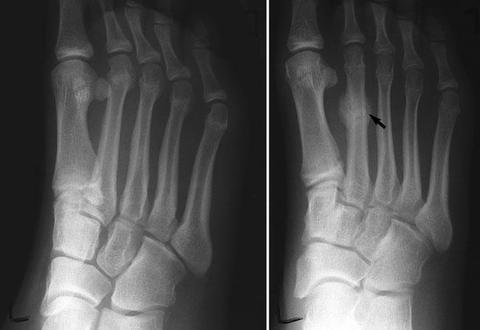

STRESS FRACTURES

STRESS FRACTURE STRESS FRACTURES A Stress Fracture is an injury to the foot bones that happens over time due to overuse instead of a sudden, sharp blow. It is...